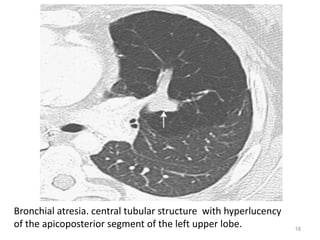

Bronchial Atresia

• Resulting in a segmental or sub-segmental bronchus becoming entirely

detached from main airway.

• Most commonly in apicoposterior segmental bronchus of the left upper

lobe.

• Distal airway will continue to produce mucus while there is no clearance

from airway.

• CT - central, mass like opacity with a tubular configuration “finger-in-

glove sign".

• Distal segmental branches are dilated and contain secretions. The

peripheral lung is hyperexpanded, with decreased attenuation and

reduced vasculature.

Bronchial atresia. central tubular structure with hyperlucency

of the apicoposterior segment of the left upper lobe.